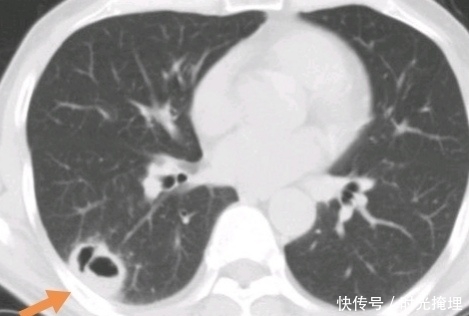

文章插图

这位病人手术后很快复发了。

如果他早一点做手术,可能结局会不一样吧。

所以很多人说,癌症早期就治疗的病人扩散更快,这个质疑是不准确的。